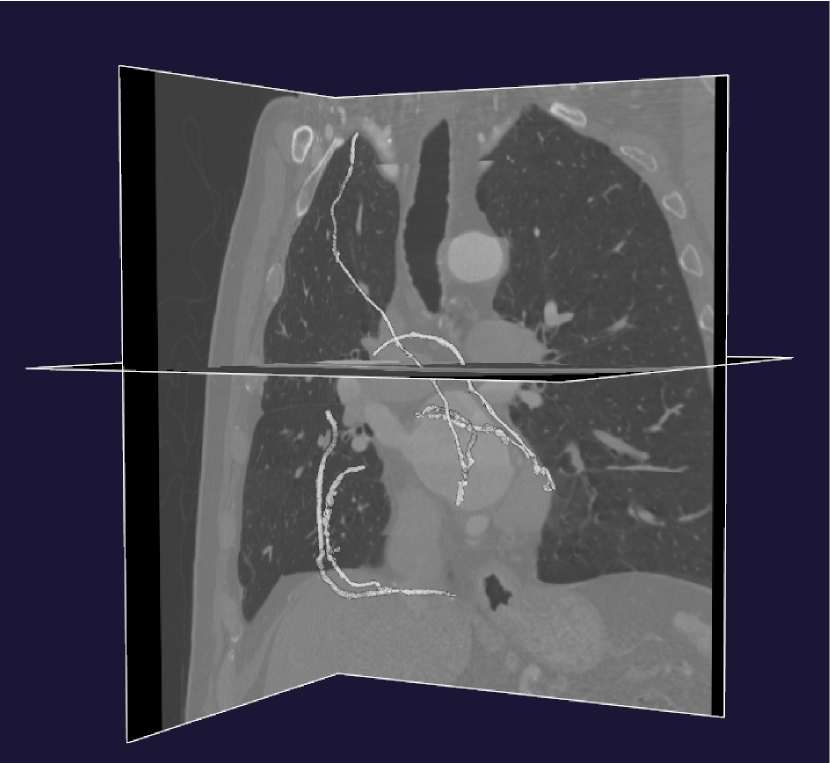

The data provided by the Sunnybrook Health Sciences Centre corresponding to this case, is a post-surgery computed tomography (CT) scan. The patient had at least three coronary arteries with occlusion ranging from mild to severe, thus, three different graft connections were made. These connections include right internal mammary artery (RIMA) grafted to bypass the blockage in left anterior descending artery (LAD) and two more connections made to first obtuse marginal artery (OM1) and posterior descending artery (PDA) separately using saphenuous veins (SV). Diseased coronary arteries and corresponding grafts, marked with different colors, are shown in figure 1.

We pre-processed the obtained medical image in order to alleviate image segmentation and geometrical reconstruction process. The pre-processing step is done in three stages, that are resampling, smoothing and enhancement, we refer the reader to Antiga et al. (Antiga et al., 2009) for details. The resampling stage aims at matching the resolution of the acquired image with the desired image segmentation process. Then, an anisotropic diffusion filter is used to reduce the high-frequency noise in the image and finally vessel enhancement filters are applied to enhance the visibility of vessel-shaped structures in comparison to other anatomical structures. Afterwards, using VMTK, we segment the pre-processed image into level sets, based on the colliding fronts approach. Then, a three-dimensional polygonal surface is generated through marching cube algorithm and is constructed by manually placing seed points according to visible intensity of the vessels. Due to the noise in clinical image and according to the visible intensity of coronary artery bypass grafts, the reconstruction process can add artificial artifacts corresponding to other parts of the cardiovascular system to the constructed geometries. We use VMTK smoothing filters to remove deformities to much extent, however the resulting tubular structures do not have sufficiently regular boundary, as is visible in the third figure, titled surface smoothed out using VMTK, in figure 2.

To generate sufficiently smooth surfaces preserving the same anatomical structures as reconstructed surfaces, we follow a centerlines-based approach (Ballarin et al., 2016, 2017). We extract centerlines, that are the lines between two sections of lumen such that their minimal distance from the boundary is maximal (Antiga et al., 2008, Piccinelli et al., 2009, Ballarin et al., 2017) using VMTK, which also outputs maximum inscribed spheres radii values associated to each point on the centerlines. After running average smoothing, we insert polyballs around the points on the centerlines according to the associated maximum inscribed spheres radii values. This yield a smooth 3D volume preserving patient-specific anatomical configuration (Ballarin et al., 2016, 2017). The algorithm is summarized in figure 2.